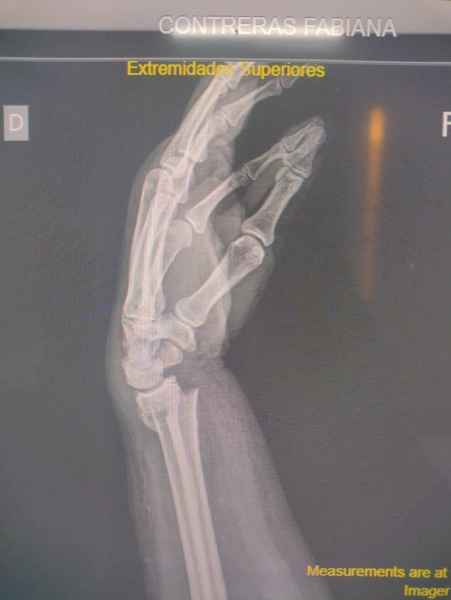

En la Artritis Reumatoidea el compromiso de las articulaciones interfalángicas proximales, metacarpofalángicas y de la muñeca estan generalemente afectadas simetricamente, lo que la distingue de la Artrosis, en la cual el compromiso se observa predominantemente en las articulaciones interfalángicas distales.

Cambios agudos como ser dolor o edema, pueden ser indicio de Artritis aguda o ataque de Gota aguda, los cambios crónicos tienden a modificar la estructura y anatomía normal de las manos como ser los dedos en cuello de cisne, mano en ventarrón, característicos de la Artritis, mientras que en la Gota crónica se observan tofos gotosos con deformidad de grandes articulaciones de la mano.